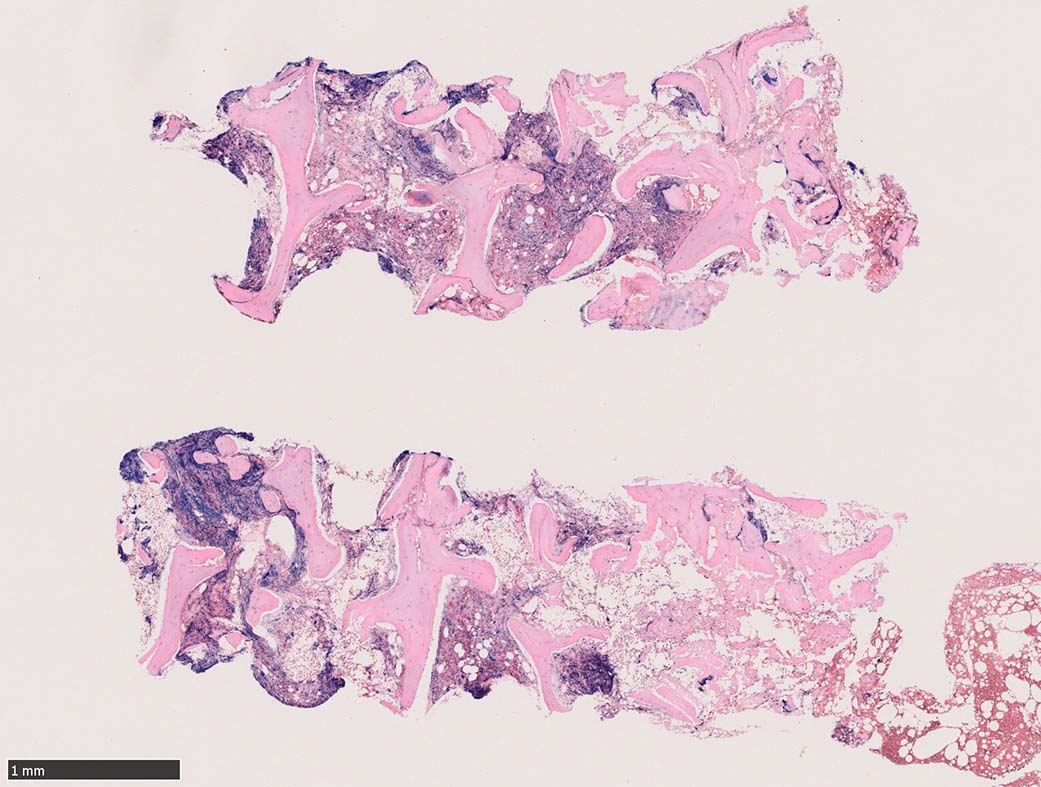

骨髄組織所見 bone marrow biopsy total 6mm in length

塗銀染色